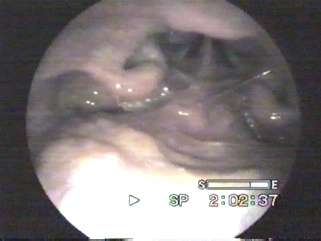

Orta kulak, kulak zarının hemen arkasında bulunan havayla dolu bir boşluktur. Kulak zarı titreştiğinde, orta kulaktaki küçük kemikçikler de titreşirler ve sesin iç kulağa, buradan da sinirler yoluyla beyine iletilmesi sağlanır. Burunun gerisindeki geniz bölgesi ile orta kulak arasında bulunan ve "östaki tüpü" adı verilen küçük bir bağlantı yolu, dış ortam ile orta kulağın basıncının aynı olmasını sağlar.

Orta kulak iltihabı ile oluşan sıvı tedavi edilmediğinde veya tekrarlayan iltihaplanmalar olduğunda orta kulaktaki sıvı birikimi sürekli hale gelebilir. Orta kulak sıvısı tek başına kulağa zarar vermez; ancak sıvı varlığında işitmede azalma olur ve orta kulakta mikropların üremesi, dolayısıyla da yeni orta kulak iltihaplarının gelişmesi kolaylaşır.

Muayenede kullanılan kulağına bakılan otoskop veya mikroskop adı verilen aletler ve gerekiyorsa işitme testleri ile tanı konur.